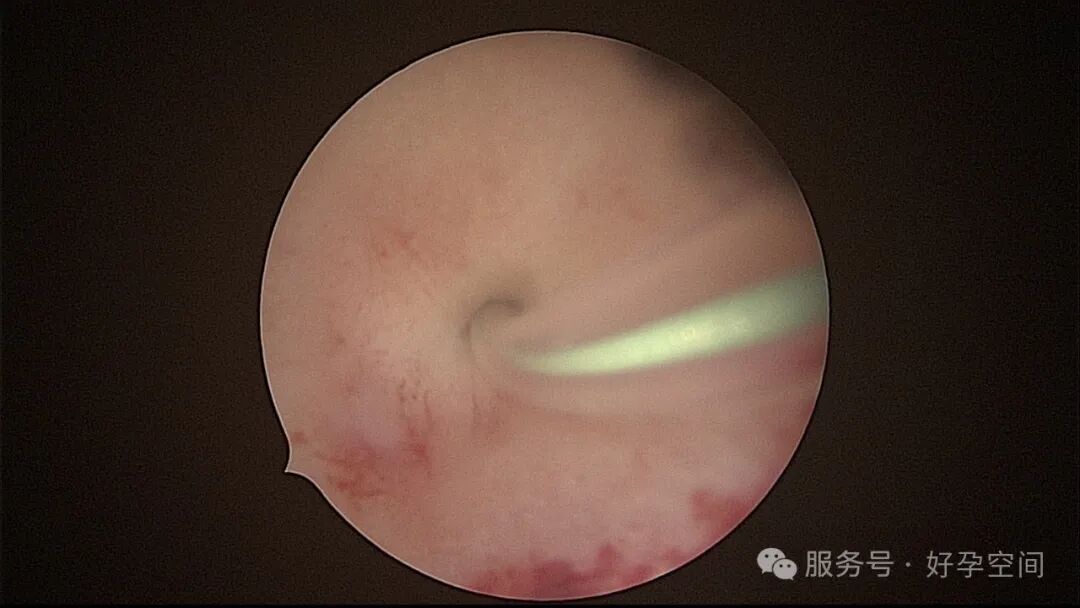

分粘后宫腔镜二探,残留少许膜性粘连,镜鞘分粘

试管前宫腔镜检查